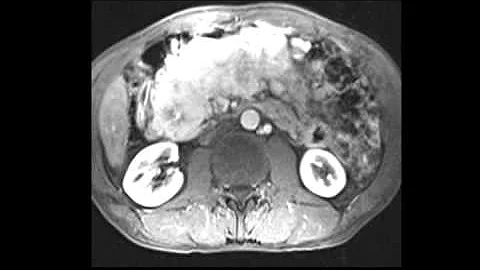

Diagnostic And Management Challenges Of Pancreatic Neuroendocrine Tumours (pnet)